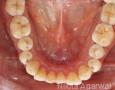

Pictures

Baseline